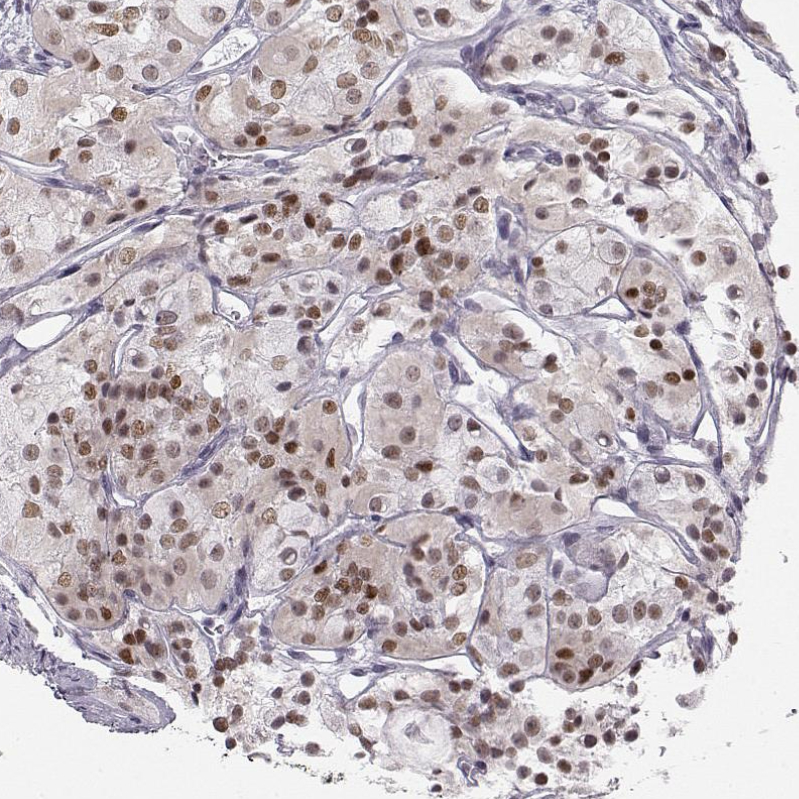

Immunohistochemical staining of human pituitary gland shows moderate nuclear positivity in anterior cells.